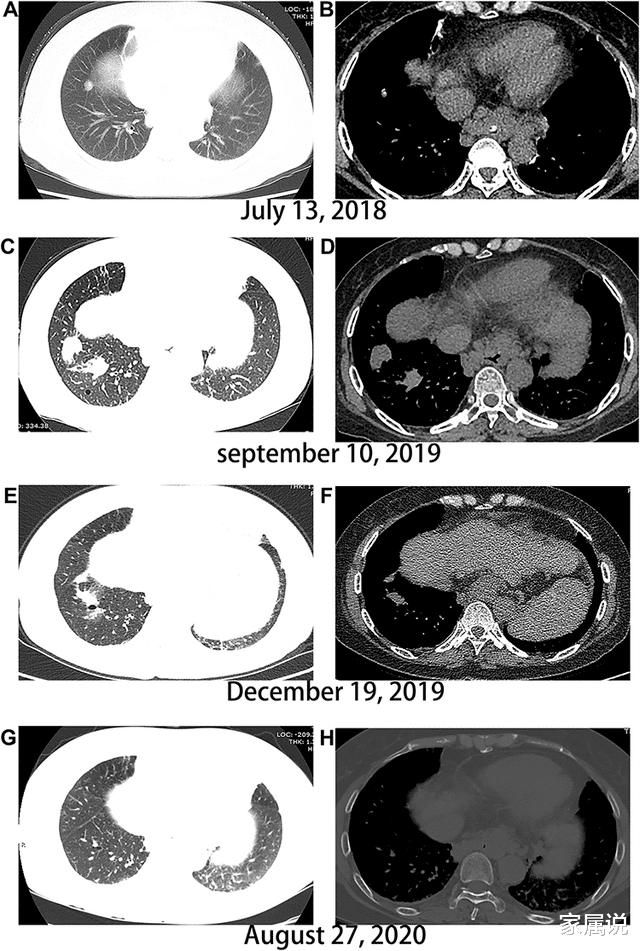

图注:肝癌肺转移的演变 。 (A、B)入院时无转移迹象 , (C、D)索拉非尼治疗1年后出现多个肺病变 , (E、F)瑞戈非尼联合信迪利单抗治疗3个月后肺病变体积减小 。 (G、H)肺转移完全缓解 。